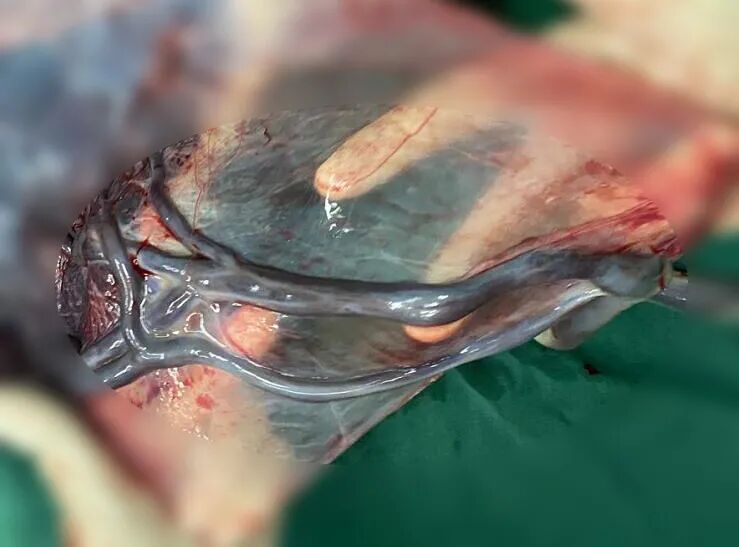

沈女士介紹,自己是頭胎,平時身體一直很好,當(dāng)?shù)弥獞言星沂请p胞胎時更是欣喜,前期產(chǎn)檢時都挺順利,但在做第一次四維彩超時被發(fā)現(xiàn)左邊胎兒帆狀胎盤前置血管?!搬t(yī)生說這種情況發(fā)生的概率很低,可一旦出現(xiàn)則很危險,若前置血管破裂,可隨時導(dǎo)致胎死宮內(nèi),寶寶很難足月出生。”得知檢查結(jié)果的沈女士既擔(dān)心又害怕,但除了告知風(fēng)險外,醫(yī)護(hù)人員一直鼓勵她樹立信心,只要配合醫(yī)生的保胎策略,相信這對可愛的雙胞胎寶寶一定能平安來到世上。隨后沈女士被市二醫(yī)院醫(yī)護(hù)人員納入高危管理,并漸漸與醫(yī)護(hù)人員建立了共同的保胎目標(biāo),在家人、醫(yī)護(hù)人員的全力支持下,順利保胎37周,生下一對體重均達(dá)5斤以上的男嬰雙胞胎,寶寶出生各項評分都很好,術(shù)中證實確實是帆狀胎盤血管前置。

據(jù)產(chǎn)科主任鄧文媛介紹,帆狀胎盤并血管前置是孕產(chǎn)婦較罕見的一種疾病。帆狀胎盤的發(fā)生率本來就低,約為0.1%~13.6% ,正常情況下,孕婦的胎盤是一個圓形,一條臍帶附著在胎盤上,緊密地將寶寶和媽媽的子宮連接在一起。但沈女士其中一個胎盤是個不規(guī)則的扇形,連接孕婦和寶寶的臍帶,并沒有乖乖地附著在胎盤上,而是附著在胎盤周圍的羊膜上,胎盤和羊膜之間布滿了密密麻麻的血管。血管前置的發(fā)病率則更低,約為1/5000-1/1275之間,指的是臍帶血管橫跨宮頸口,在寶寶先露的前方,如果在分娩前,存在血管前置而沒有發(fā)現(xiàn),在臨產(chǎn)前后,胎膜破裂就會引起前置的血管發(fā)生撕裂,導(dǎo)致寶寶的急性出血,嚴(yán)重危害寶寶的安全,死亡率可達(dá)60%,即使經(jīng)過搶救,寶寶仍然可能會留下比較嚴(yán)重的后遺癥。